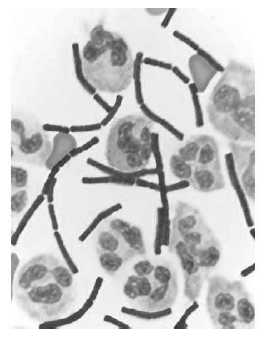

A figura precedente mostra o fluido cérebro-espinhal de um paciente com infecção bacteriana. Considerando essa informação e os múltiplos aspectos a ela relacionados, julgue o item a seguir.

Considerando-se a forma da bactéria e o fato de ela estar presente no fluido cérebro-espinhal, deve-se realizar prova de Gram nessa amostra para a confirmação da infecção por Neisseria meningitidis.

Antraz, doença que já foi explorada como arma biológica, é causada por uma bactéria que apresenta a forma do microrganismo mostrado na figura.

O resultado positivo para a presença de bactéria gram-positiva nesse fluido significa que a bactéria possui uma camada fina de peptidoglicano e uma membrana externa com lipopolissacarídeo, fosfolipídios e proteínas.